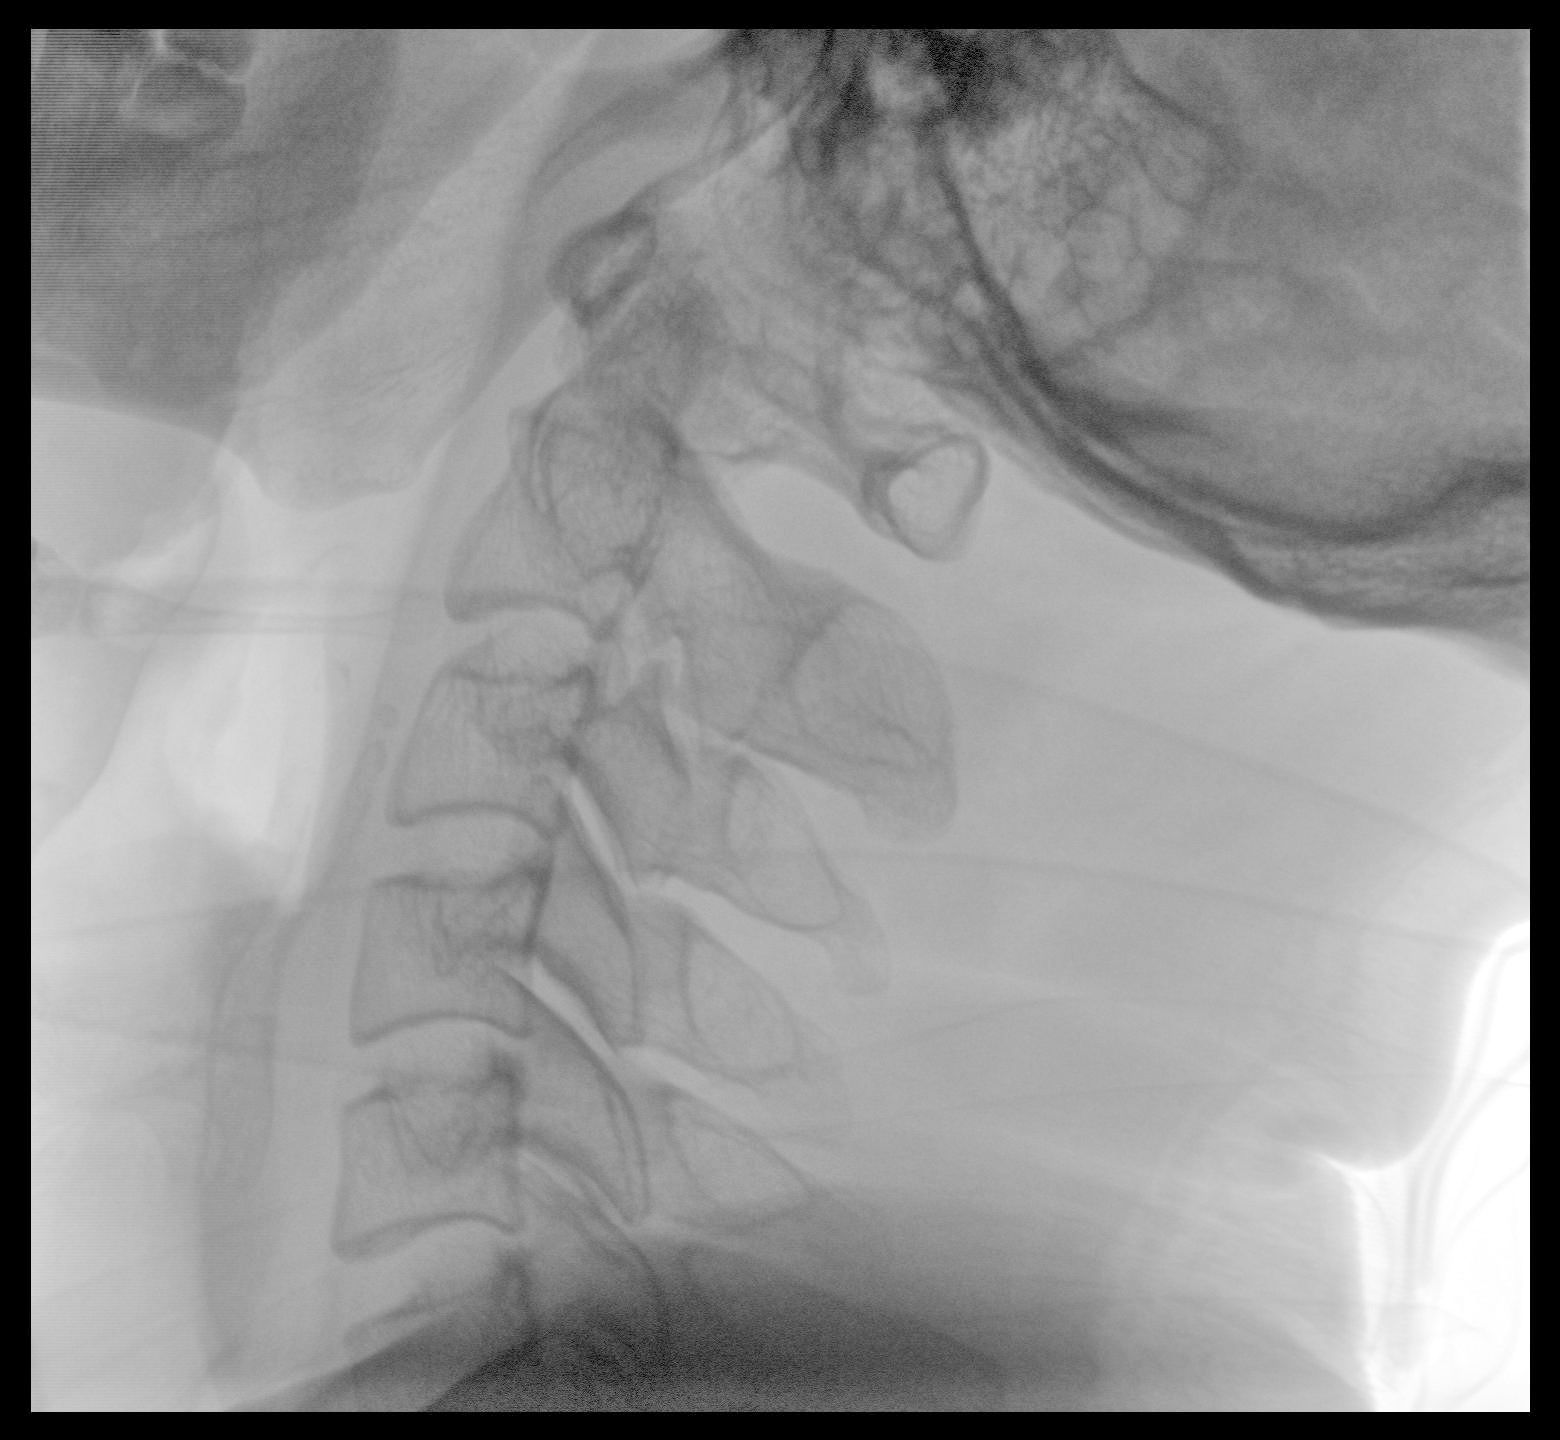

Clinical picture

臨床圖片